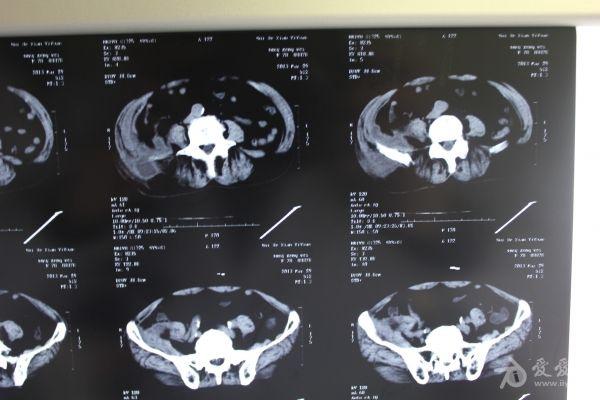

老年患者78岁,反复腰背部溃烂流脓4年,既往30年前曾在包块处排出蛔虫一条。CT: